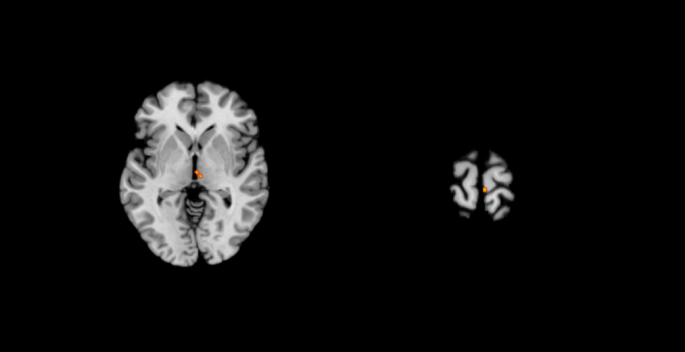

Across 3 studies30,31,32 (with a total of 13 foci included) reporting a significant decrease in brain activation specifically related to working memory during sport intervention, significant convergence was observed in the right thalamus and the right paracentral lobule. No cluster was observed to have increased activation30,33,34,35as shown in Table 6; Fig. 4.

Activation clusters for working memory ALE analysis in standard MNI space.

In the deactivated brain regions, 2 studies31,32 (with a total of 10 foci included) were included in the chronic exercise group, and the results revealed significant convergence of working memory tasks in the right thalamus(Some coordinates from the same article with older adult subgroup).

Deactivation clusters for working memory ALE analysis in standard MNI space. (a) Older adult. (b) Chronic exercise.